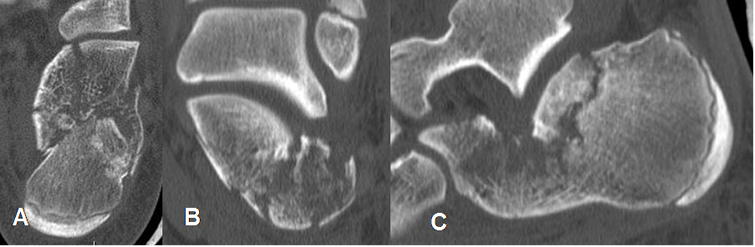

Fig 47. Fractura del calcáneo.

A: Rx lateral y B: TAC axial de calcáneo. Fractura impactada y conminuta del calcáneo, con un ángulo de Bohler negativo.

C: TAC reconstrucción lateral. Fractura asociada en el cuerpo de D12.